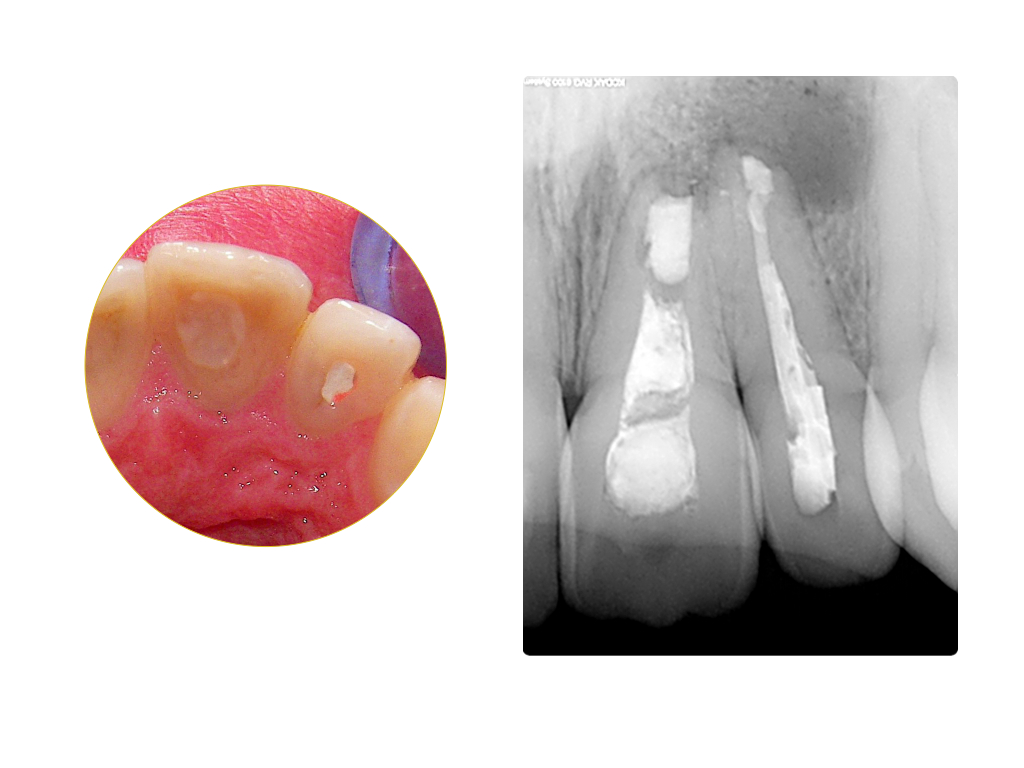

Einbahnstraße WSR (2)

Ausgangssituation